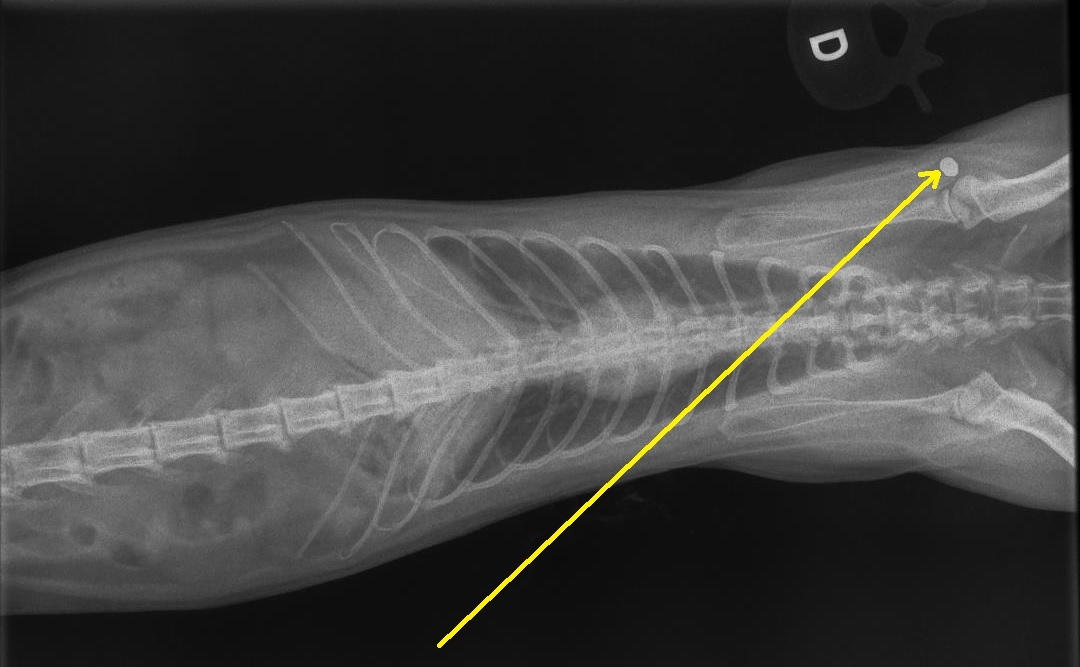

| Dire merci | non non, il était tigré, tout bêtement. Et puis gentil, mais gentil! et celle-là, elle était tricolore, reçue en urgence un soir, détresse respiratoire intense...j'ai juste trouvé un petit trou au niveau du thorax...radio...et bim.... ![]() en jaune, j'ai matérialisé le trajet de la balle.... nul besoin de vous dire que la minette n'a pas survécu longtemps après mon diagnostic ![]() |